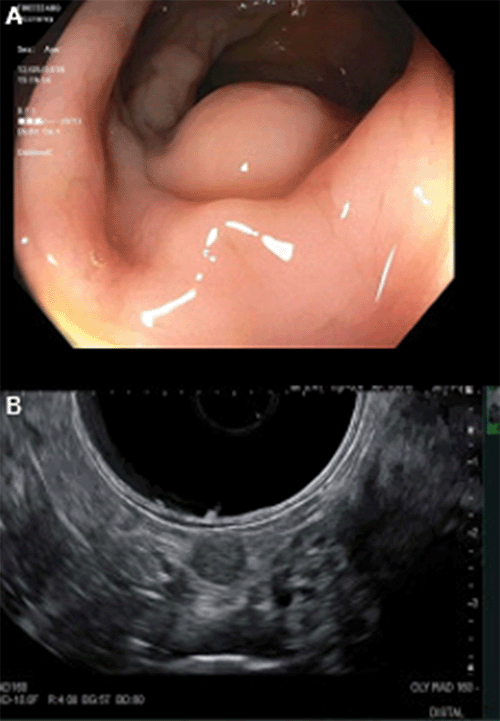

The patient underwent an eventual colonoscopy and endoscopic ultrasound, which identified a 2 × 2 cm non-circumferential submucosal mass in the sigmoid colon, approximately 30 cm from the anal verge, with associated clusters of lymphadenopathy (Figure 2). These perirectal lymph nodes were as large as 9 mm in diameter and appeared hypoechoic and heterogeneous with well-defined endosonographic borders. Superficial colonoscopic biopsy with cold forceps was non-diagnostic. Interventional CT-guided fine-needle aspiration was attempted but aborted due to limited percutaneous accessibility.

Figure 2. Endoscopic Findings of Rectosigmoid Mass. Published With Permission

A) Colonoscopy with evidence of endoluminal protrusion of sigmoid mass; and B) endoscopic ultrasound highlighting abnormal perirectal lymphadenopathy.